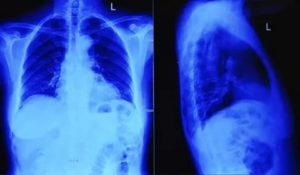

Простой острый бронхит увидеть на рентгеновском снимке невозможно, визуализации поддаются только обструктивные и хронические длительно текущие формы заболевания. Рассмотрим примеры того, как выглядит бронхит на рентгеновских снимках:

На фото 1 и 2 видно, как выглядит бронхит на рентгеновских снимках, а точнее, признаками заболевания являются:

- изменение размера и структуры корней легких,

- нечеткость его контуров,

- изменение легочного рисунка (как правило, усиление),

- утолщение стенок бронхов при хроническом бронхите (симптом «трамвайные рельсы» фото 3).

Важно! На обычном рентгеновском снимке легких можно рассмотреть только трахею и крупные бронхи, мелкие бронхи не видны.

Еще одной особенностью бронхита является диффузность поражения, то есть вовлечение в процесс обоих легких.